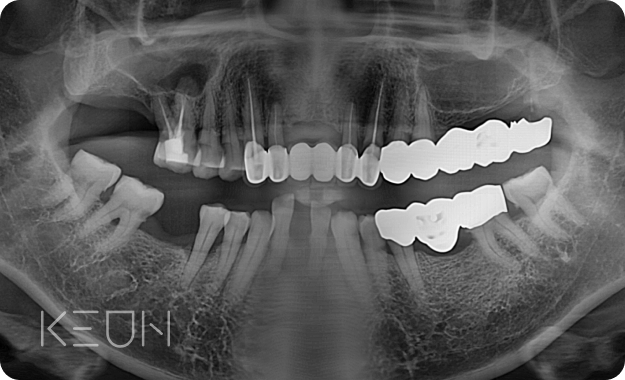

뼈이식 임플란트 전후사진.

- Before

- After

*모든 치료전/후 사진은 환자분의 동의하에 촬영 및 게시되었습니다.